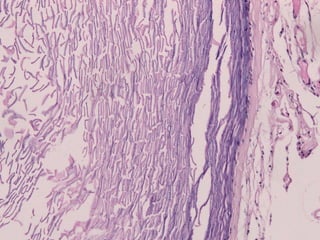

• Made up of connective tissue

Connective Tissue

is dense

Reticular

Layer

Thick fibre

bundles & elastic

Thick skin of

palms and soles

fibres

Interval between

the fibre bundles

are occupied by

adipose tissue.